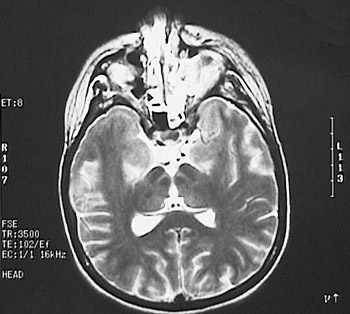

These MRI scans of the head reveal an irregular enhancing area of

mucormycosis

on the left. There is overlying

soft tissue swelling

. One of the views below indicate the result of treatment of this condition--radical surgical excision.